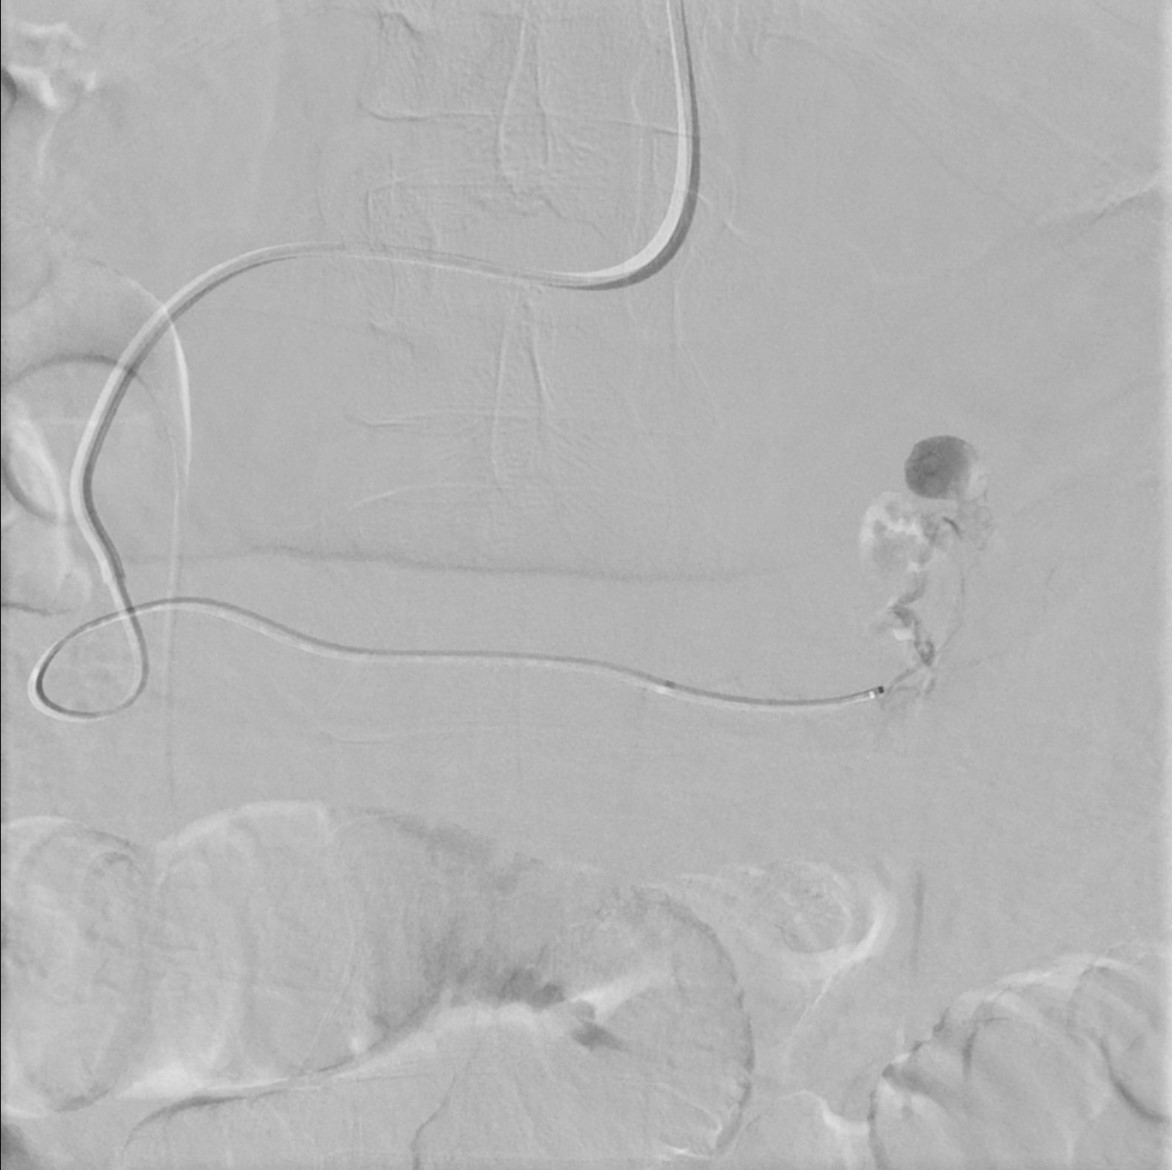

Left gluteal active extrav seen on trauma CT, followed by embolization of an inferior gluteal muscular branch. Follow up CT demonstrates appropriately positioned coils without further extrav. #IRad #TwittIR #VIrad